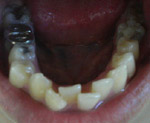

五歳の娘ですが、乳歯の時より受け口で、気にはなって歯科院で定期健診をしていました。すでに、下の前歯4本が永久歯に生え変わり、六歳臼歯が生えると、上下のズレが出てきて、5ミリ以上ずれています。

すでに、下の前歯4本が永久歯に生え変わり、六歳臼歯が生えると、上下のズレが出てきて、5ミリ以上ずれています。

今、上の前歯2本が生えてきている状態で、拡大装置とチンキャップをしていますが、先生が将来、外科矯正が必要になりそうですと言われ、かなり落ち込んでいます。

写真を拝見したところ、あなたの状態は受け口の傾向を持つ叢生(でこぼこ)ケースと思われます。